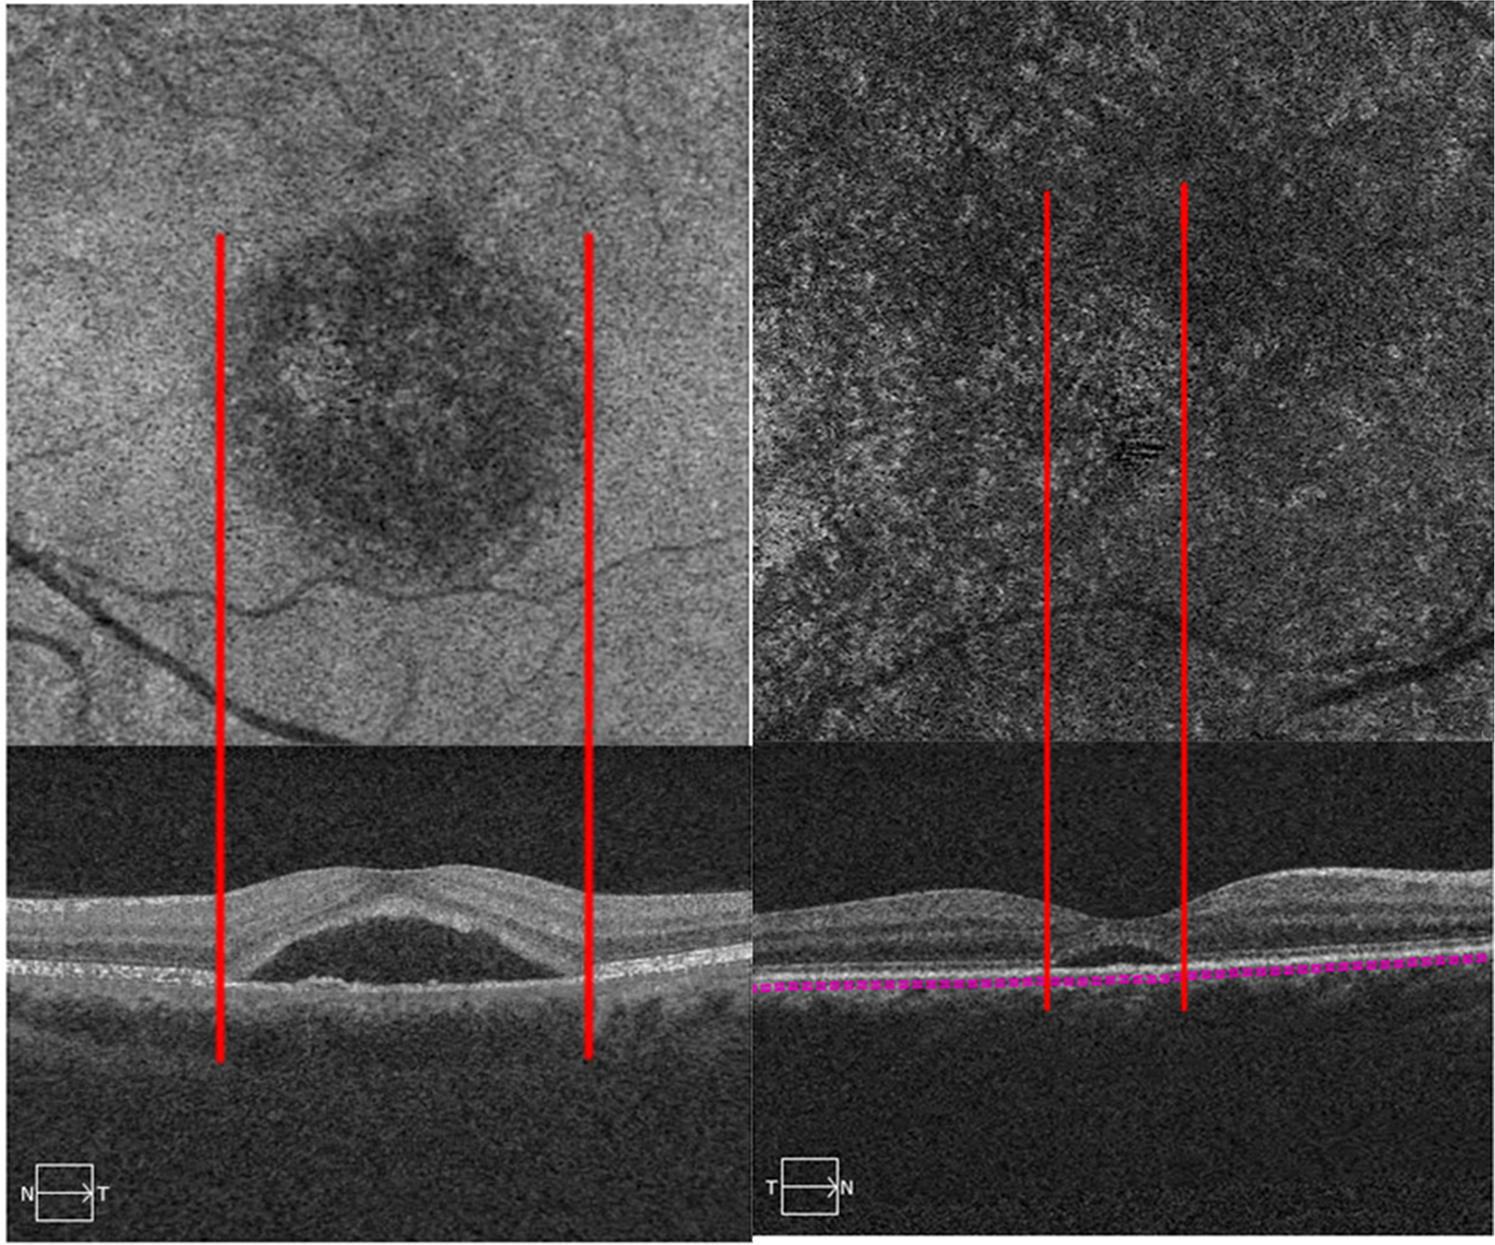

Figure 4

En face choriocapillaris optical coherence tomography angiography (OCTA) images and the B-scan of the same central serous chorioretinopathy (CSC) patients. Patient with type B (left panel) showed the extent of subretinal fluid (SRF) on B-scan corresponding with the area of type B abnormalities on OCTA. Patients with a thinner SRF did not exhibit the corresponding halo on OCTA (right panel).